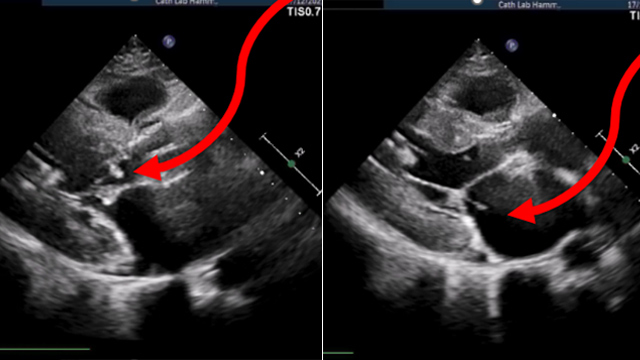

Focusing on thrombotic complications following transcatheter valve implantation, this session presents a series of complex cases illustrating acute and late thrombotic events, their clinical presentations, and the pivotal role of multimodality imaging in diagnosis and management. Insights include coronary embolism and cardiogenic shock scenarios, emphasizing challenges...

This session reviews unusual and severe complications encountered during TAVI procedures, such as aorto-right ventricular fistula, ventricular perforation, and sinus of Valsalva rupture. It highlights percutaneous treatment successes and endovascular interventions, offering critical insights into managing life-threatening procedural complications effectively.